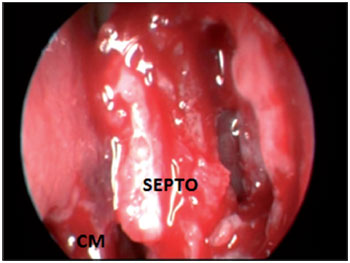

Figure 2. Video-endoscopic visualization of the left nasal cavity showing the septal incision site and opening of the bone wall of the pneumatized crista galli. SEPTO = nasal septum; CM = middle turbinate; CI = inferior turbinate.

Figure 4. Intraoperative endoscopic visualization of the right nasal cavity showing septal incision and detachment.

SEPTO = nasal septum; CM = middle turbinate.